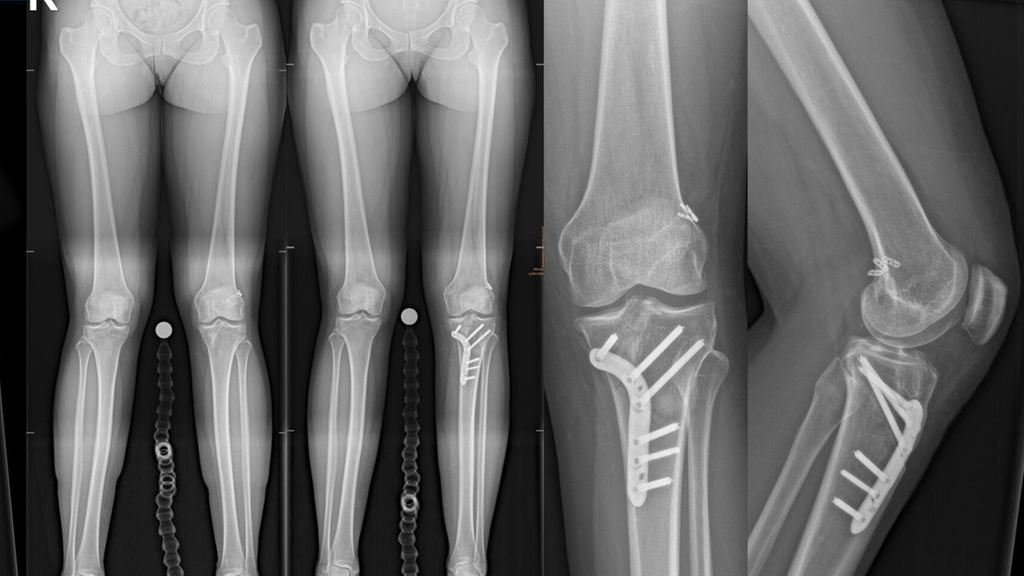

Abb. 3: 33-jährige weibliche Patientin mit zweifacher VKB-Reruptur (A) mit einem erhöhten tibialen Slope von 15° (B) und einer Valgusfehlstellung von 3° (C), behandelt mit einer einzeitigen Revision mitipsilateralem Quadricepssehnengraft und einer varisierenden Slope-reduzierenden HTO (D, E, F)